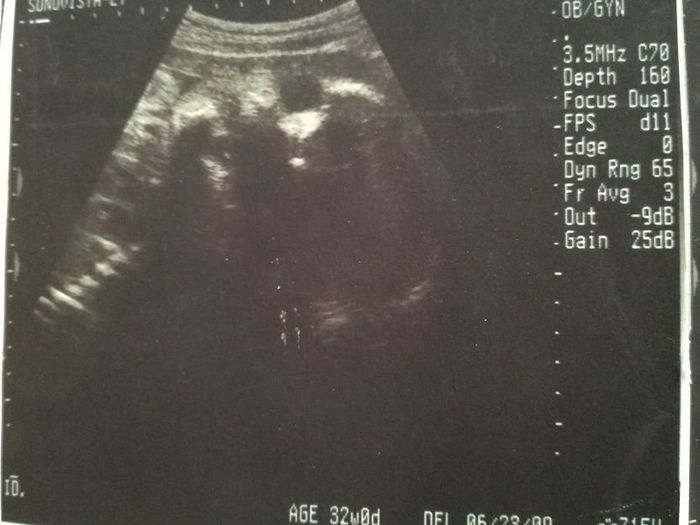

妊娠32週目のエコー写真

推定体重1803g。「平均的だから、成長も問題ない」と先生から説明を受けました。赤ちゃんは性別をまだまだ内緒にしているよう。出産も近づきつつあるこの時期、動けるときは運動を兼ねてお散歩したり、劇場などで開かれるランチタイムコンサートなどに行ったりしました。音楽と共に胎動を感じるときは、我が子と一心同体でその瞬間を楽しんでいるような幸せな心地がしました。